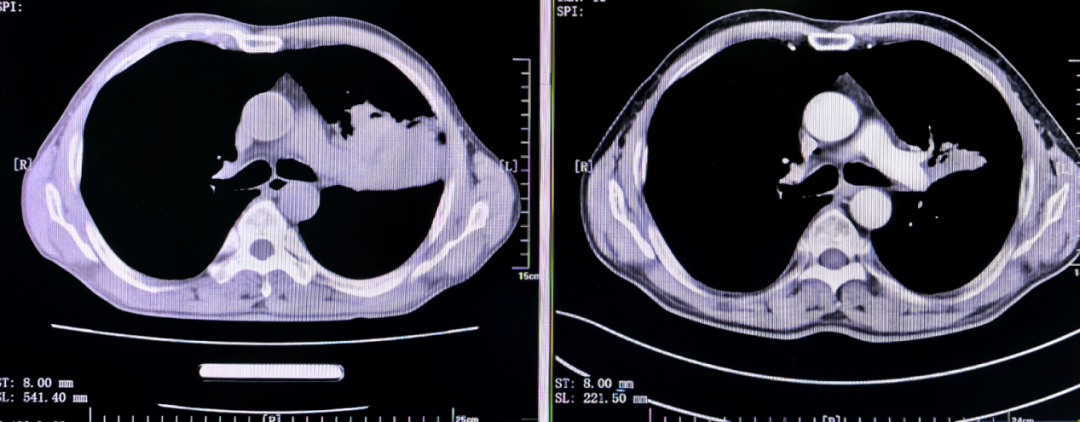

2023 年初,王先生因持续咳嗽、发热来到医院就诊。CT 影像显示:左肺上叶一片模糊,肿瘤阻塞了支气管,导致远端肺叶塌陷——医学上称为「肺不张」。

治疗两个周期后,王先生的复查 CT 显示:左肺上叶不张明显缓解,肿瘤显著缩小。

虽然肿瘤已明显缩小,达到了可手术状态。但手术仍面临巨大挑战——肿瘤与肺动脉的距离仍然很近。

「虽然新辅助治疗后肿瘤缩小,但仍紧贴肺动脉主干,直接切除可能导致血管缺损、大出血等风险。所以,我们需要行肺动脉成形术。这是胸外科的高难度技术之一。」戴云说道。